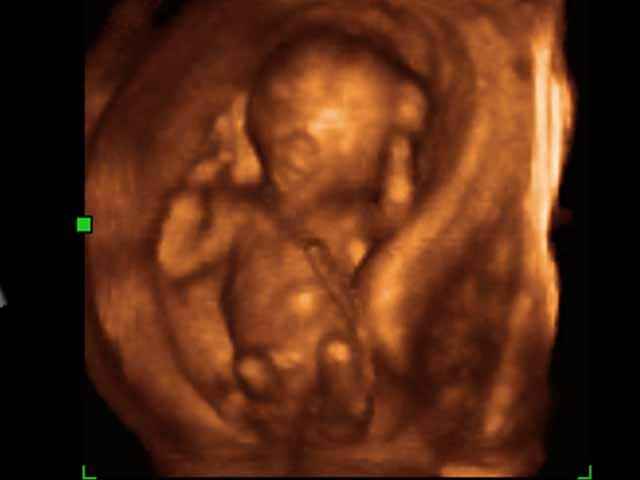

- 3D Photos Ecographie du Premier Trimestre

3D Photos Ecographie du Premier Trimestre (Photos d’échographie de tôt grossesse)| Dr N Layyous